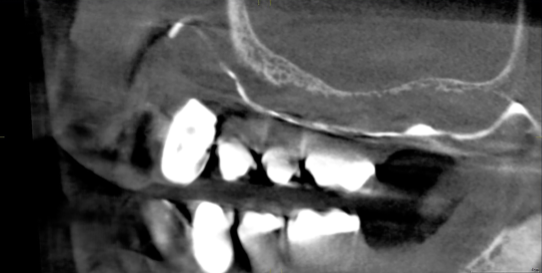

Un paziente maschio di 58 anni (Fig. 1), senza anamnesi medica rilevante, si presenta alla nostra attenzione richiedendo una riabilitazione protesica fissa su impianti alle due arcate. L’edentulia e l’atrofia ossea all’arcata superiore, come verosimile risultato di parodontite cronica dell’adulto, e la presenza di tre denti e due impianti con una prognosi parodontale infausta, sono evidenti all’esame clinico e nelle immagini radiologiche (Fig. 2), così com’è visibile l’incongruenza delle protesi rimovibili, con estetica compromessa e malocclusione in cross bite monolaterale (Fig. 3), con segni e sintomi disfunzionali.